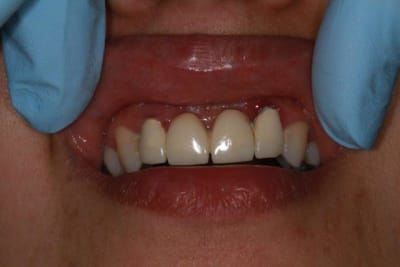

sur-traitement, pompe à fric, assassinat ...etc.. afin d'éviter tout ça je soumet à votre sagesse un cas sympa.

Patiente sympa, 30 ans, un bridge ceramo-métal fait il y a 10 ans, en fin de vie.

En réalité je sais déjà ce que je vais faire, mais implants, bridge ou pourquoi pas adjointe???

Bon choix mais si implants 11/21 bridge avec extensions latérales...je ne suis pas fan.

Par contre implants 12/22 et bridge ça devient raisonnable (pour moi)mais il faut enlever 12/22 et faire une pap pour les provisoires.

En général, implant 12-22 c'est plus sympa que 11-21 et des extensions.

Alors exo et implants 12-22, greffe en vestibulaire (os et muco), question de blinder le tout.

Pareil pour 11 et 21, avec greffe en vestibulaire pour garder un bon axe si nécessaire.

C'est toujours mieux de poser en 11 et 21, meilleur profil d'émergence et gestion des papilles + facile.